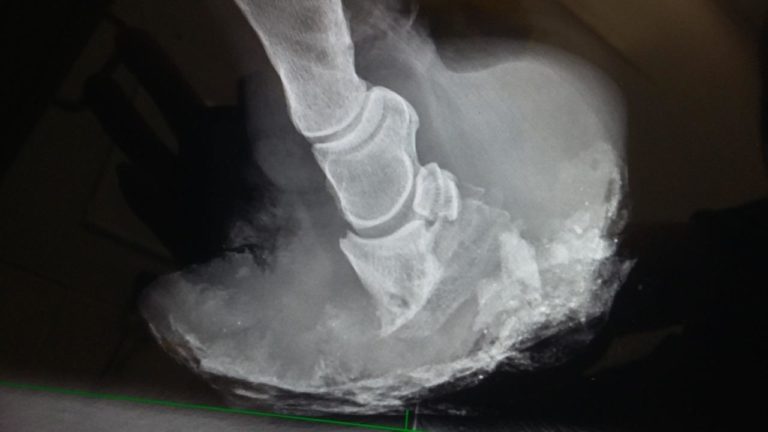

Alfie laminitis radiograph